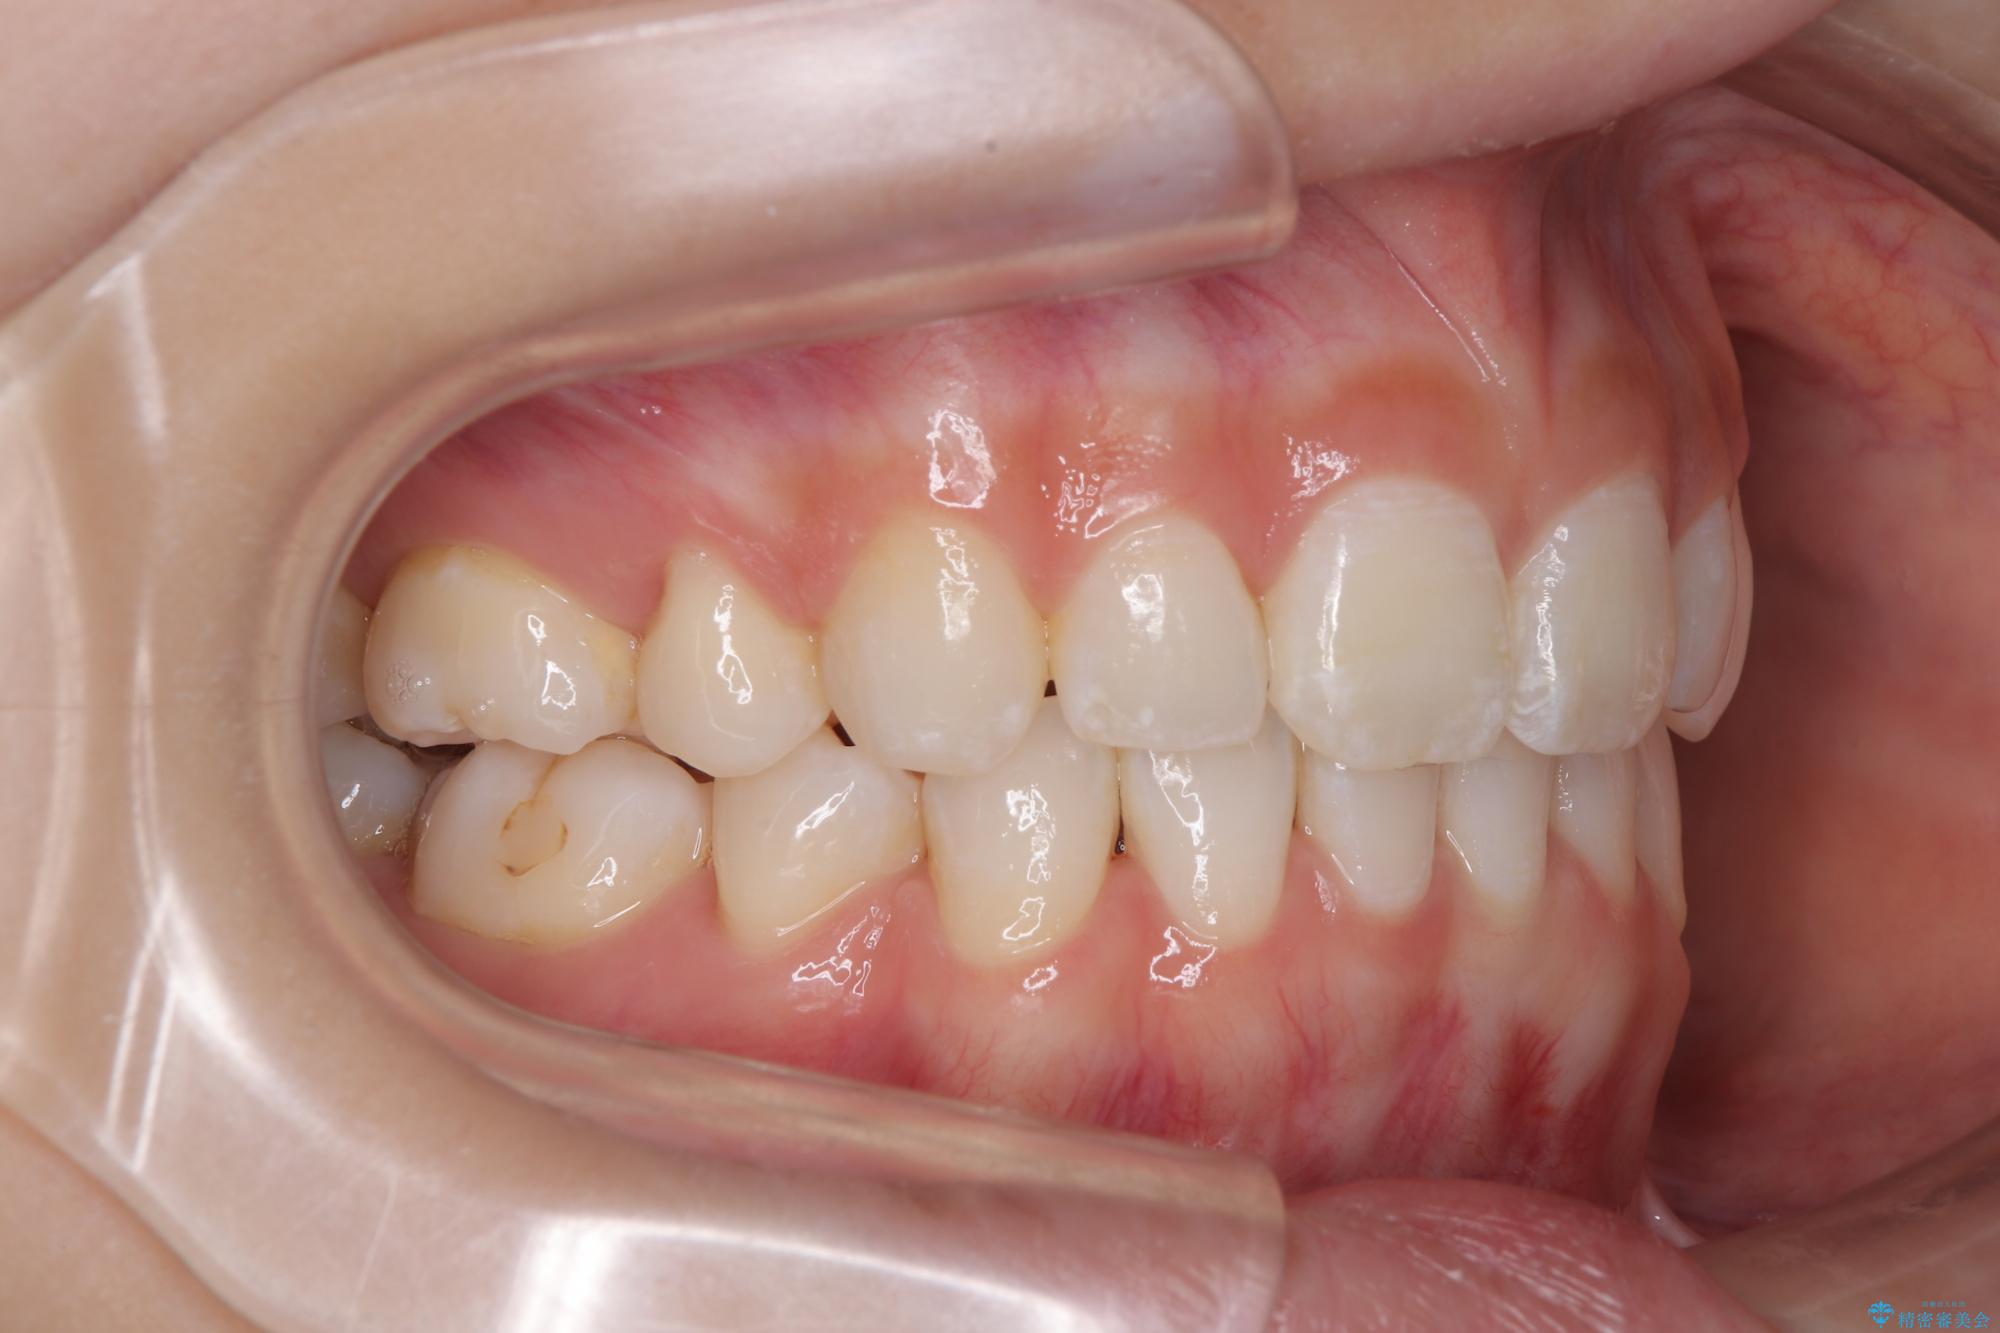

- 口を閉じたときに飛び出してしまう上顎前歯を気にして来院された患者様です。

下顎はデコボコが気になっていたため、上下左右第一小臼歯4本を抜去して、ワイヤー装置にて口元の突出感を改善するよう矯正治療を行うこととしました。

下唇に前歯が当たって跡が残ってしまう状態でしたが、スッキリとした口元に仕上げることができました。